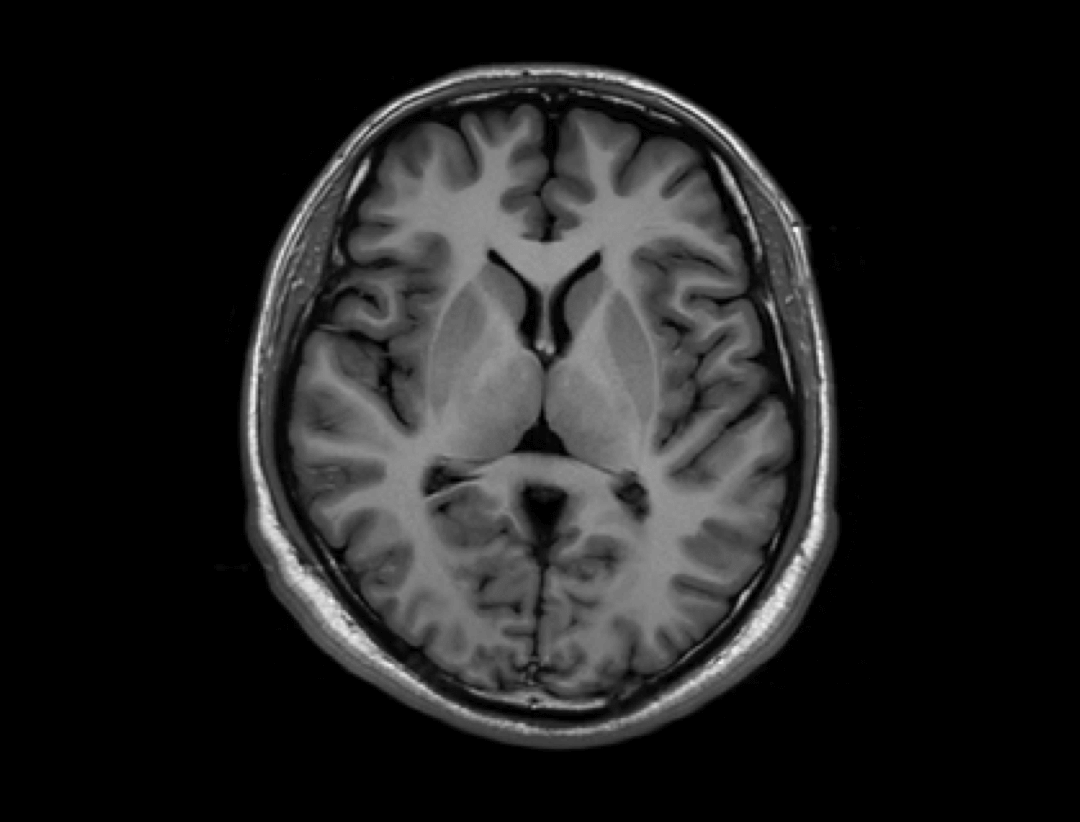

Dzięki opracowanej przez UIH technologii korekty uMR®580 cechuje się doskonałą jednorodnością pola magnetycznego.

Inteligentna technologia kompensacji prądów wirowych zapewnia wysokie parametry gradientów uMR®580.